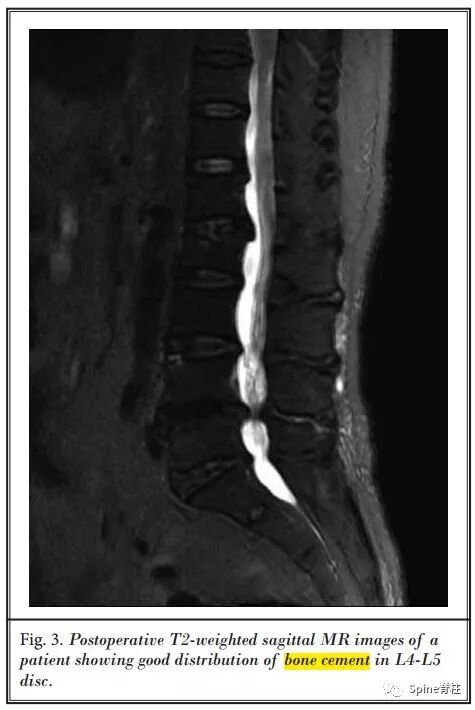

回顾性分析28例(112椎间盘)单节段或多节段PCD治疗严重腰椎间盘退变引起的轴性腰痛和功能障碍的临床资料。全部采用全麻,经Kambin三角椎间盘造影入路注入高粘度PMMA骨水泥。

术后骶骨倾斜角和骨盆倾斜角均明显减小,腰椎节段和整体前凸角、椎间盘和椎间孔高度均明显增加。随访6个月,VAS和ODI评分较术前显著改善,且腰痛的改善程度与节段性侧凸矫正明显相关,且无明显并发症的发生。

最后,作者得出结论,PCD是一种治疗严重椎间盘退变引起轴性腰痛和功能障碍的有效微创方法,不但可纠正腰椎侧凸,而且可达到椎间孔间接减压的效果。对于伴有多种内科疾病且不宜行开放手术的老年患者,PCD是一种选择。